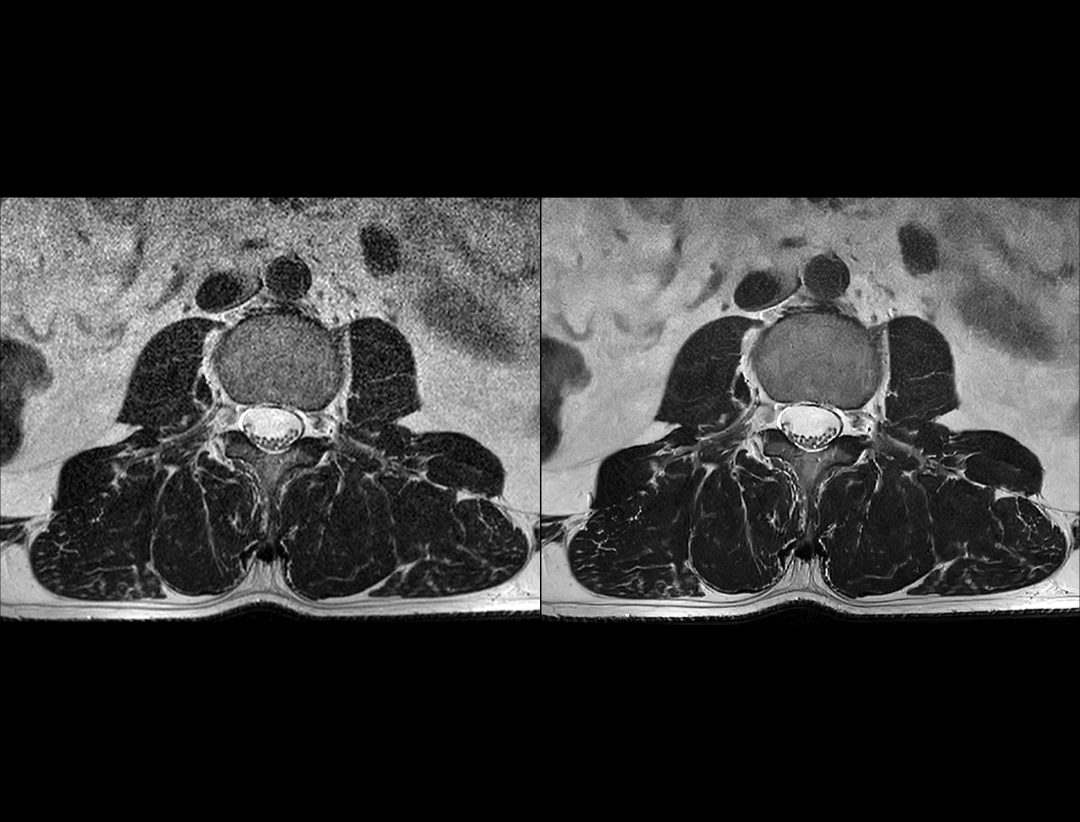

高信噪比

常规临床型1.5T (1:42 min) vs. uMR 660 (1:42 min)

0.46×0.42×4 mm3